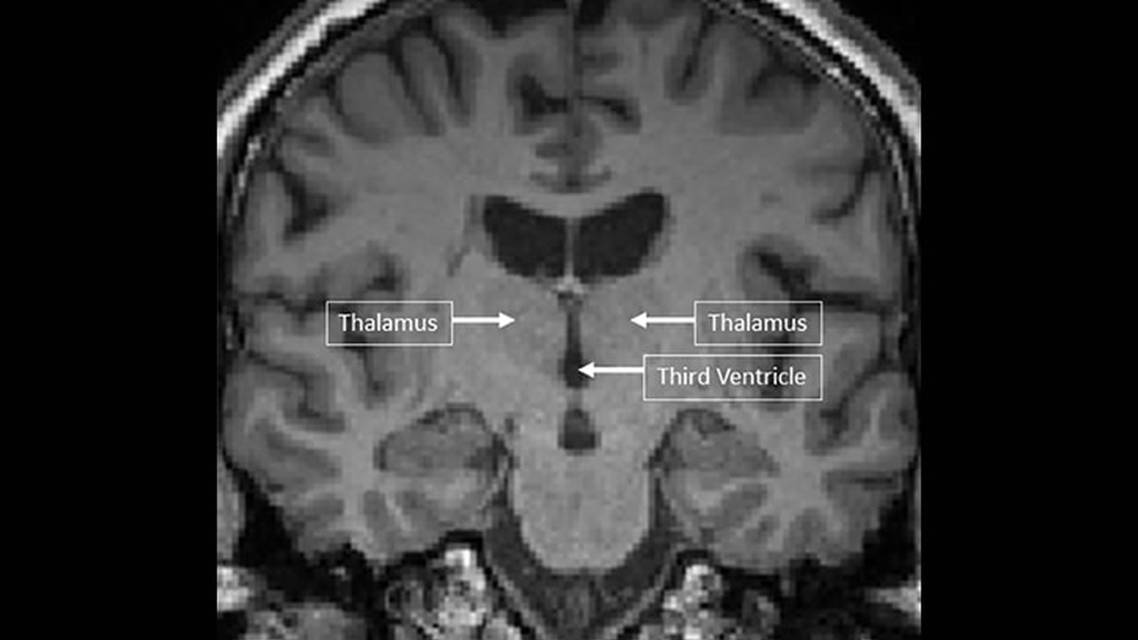

Cognitive deficits correlate with structural and functional MRI indices. Brain metrics, such as total lesion volume and total white and gray matter volume, are modestly associated with cognitive deficits. The most robust structural index associated with cognitive impairment is thalamic volume.10 This is not routinely measured in a clinical setting, but an indirect marker of thalamic size may be found from inspection of the third ventricle, given the close proximity of the thalamus. Indeed, one of the earliest brain imaging–cognitive studies that predates the MRI era reported a fairly robust association between the width of the third ventricle and indices of visual and verbal memory.11 Subsequent, more sophisticated MRI brain volume metric measurements have confirmed this.12 The width of the third ventricle is a potentially useful clinical MRI marker of thalamic integrity (Figure 2).